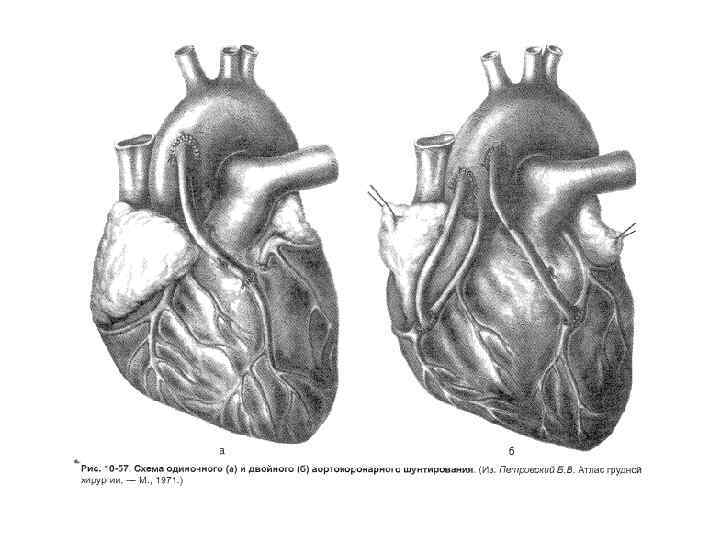

Аортокоронарное шунтирование • Техника. Продольная стернотомия (мягкие ткани послойно рассекают по срединной линии вдоль всей грудины) стернотомом. • Края грудины разводят расширителем.

Аортокоронарное шунтирование • Техника. Продольная стернотомия (мягкие ткани послойно рассекают по срединной линии вдоль всей грудины) стернотомом. • Края грудины разводят расширителем.

• В качестве сосудистого трансплантанта в большинстве случаев используют сегменты большой подкожной вены бедра.

• В качестве сосудистого трансплантанта в большинстве случаев используют сегменты большой подкожной вены бедра.

• Проводится при многососудистом поражении венечных артерий - 3 и более - проксимальных коронарных артерий, при стволовом стенозе ЛКА. • Одновременно можно шунтировать до 4 венечных артерий. • Результаты АКШ определяются: 1) проходимостью шунтов, 2) состоянием периферического русла венечной артерии у реципиента

• Проводится при многососудистом поражении венечных артерий - 3 и более - проксимальных коронарных артерий, при стволовом стенозе ЛКА. • Одновременно можно шунтировать до 4 венечных артерий. • Результаты АКШ определяются: 1) проходимостью шунтов, 2) состоянием периферического русла венечной артерии у реципиента